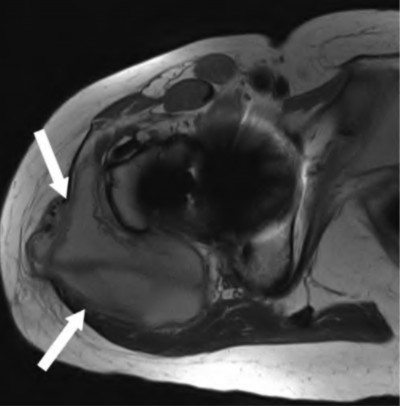

A 62-year-old male presents with groin pain and a palpable mass 5 years after receiving a metal-on-polyethylene total hip arthroplasty with a large diameter modular cobalt-chromium head on a titanium stem. Serum cobalt levels are significantly elevated while chromium levels are mildly elevated. A metal artifact reduction sequence (MARS) MRI shows a cystic pseudotumor. What is the most likely diagnosis?

Explanation